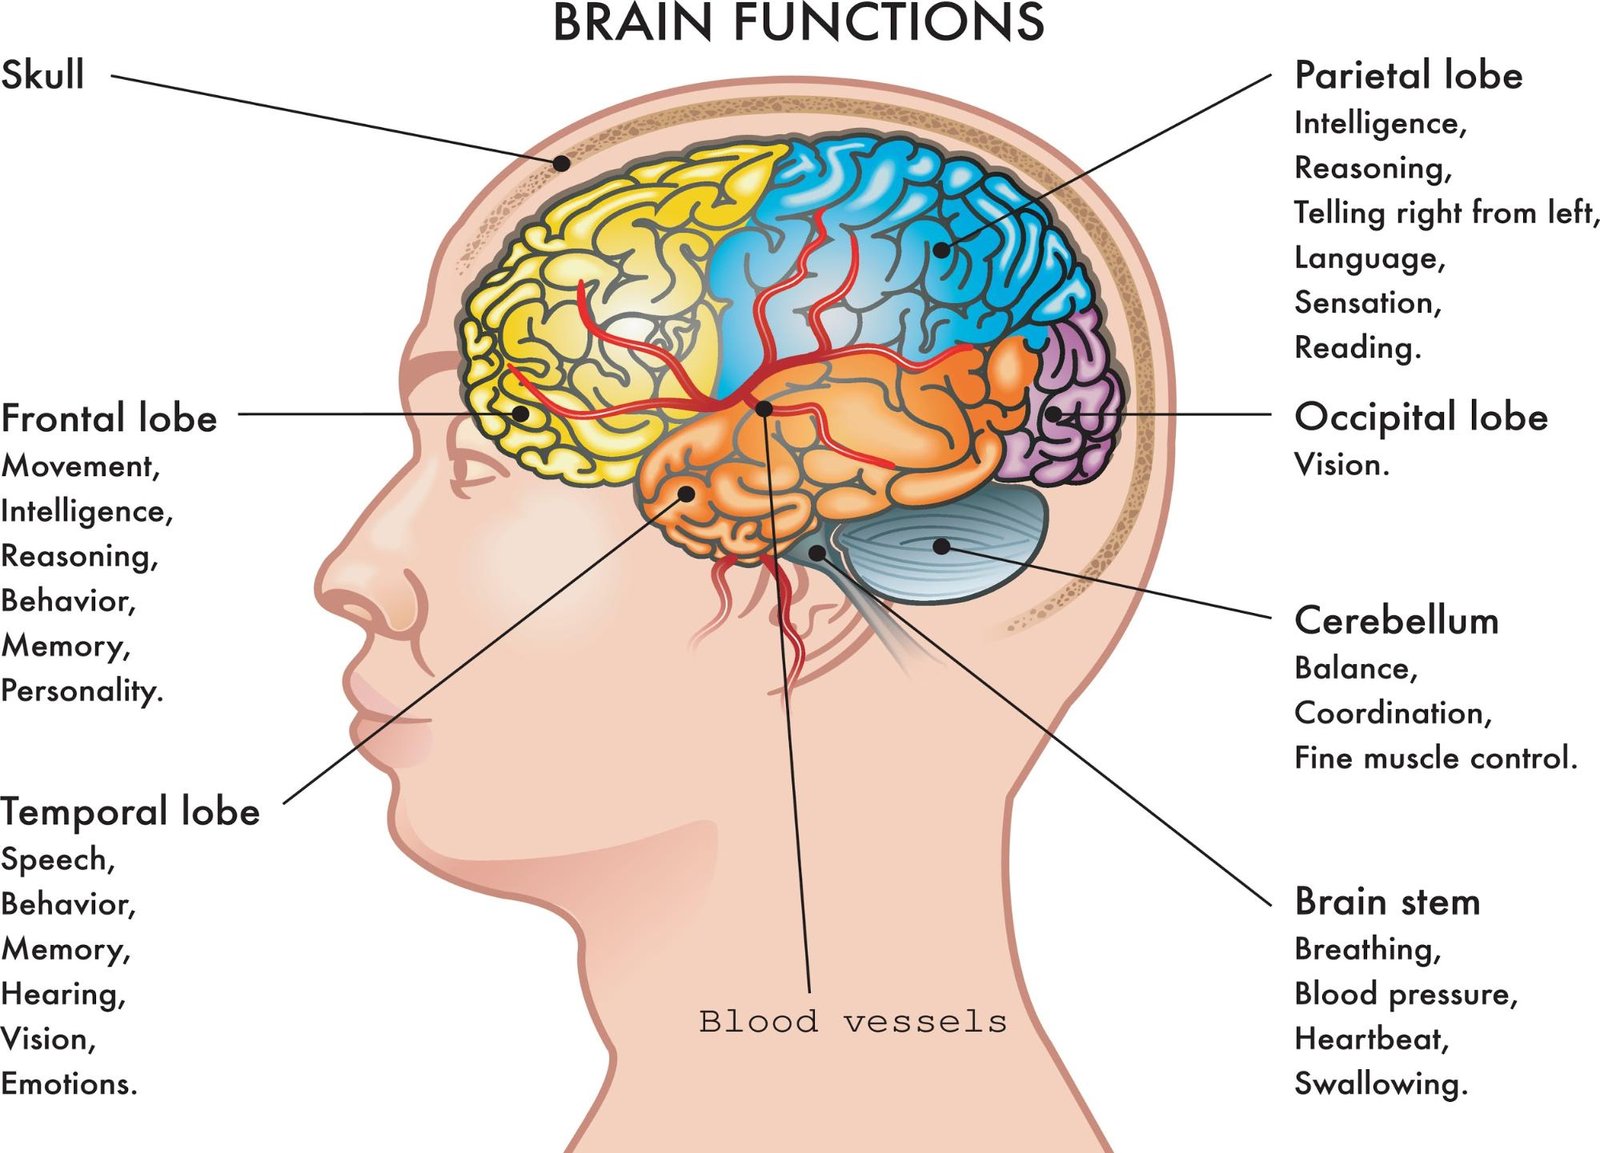

1. Skull Fractures

Skull fractures are caused by a severe impact to the head, as can happen in sports, car accidents, and slip and fall accidents. A fall victim with a skull fracture often has additional head and brain injuries arising from the fall.

There are four types of skull fractures:

- Simple – a crack in the bone without damage to the skin

- Linear – a thin line break without splintering, depression, or distortion of bone

- Depressed – a break or crushed portion of the skull with depression of the bone toward the brain

- Compound – involves damage to the skin and splintering of the skull bone

2. Intracranial Hematomas

Intracranial means inside the head. Intracranial hematomas are blood pools or clots that form on or in the brain after a blow to the head.

3. Traumatic Brain Injuries

The effects of Traumatic Brain Injury (TBI) can range from mild to disastrous and life-altering. On the milder end, the patient might experience a few days of headaches and dizziness. More severe symptoms include coma, seizures, loss of body control, and behavioral changes.